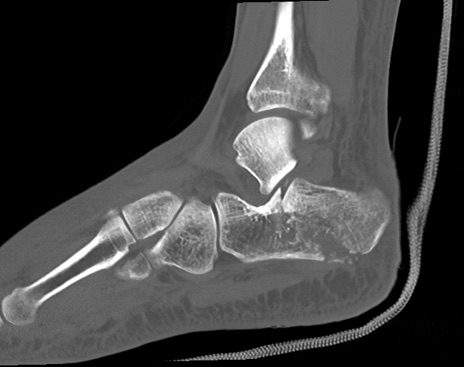

症例37 左足関節CT(矢状断像)

左足関節CT

冠状断像